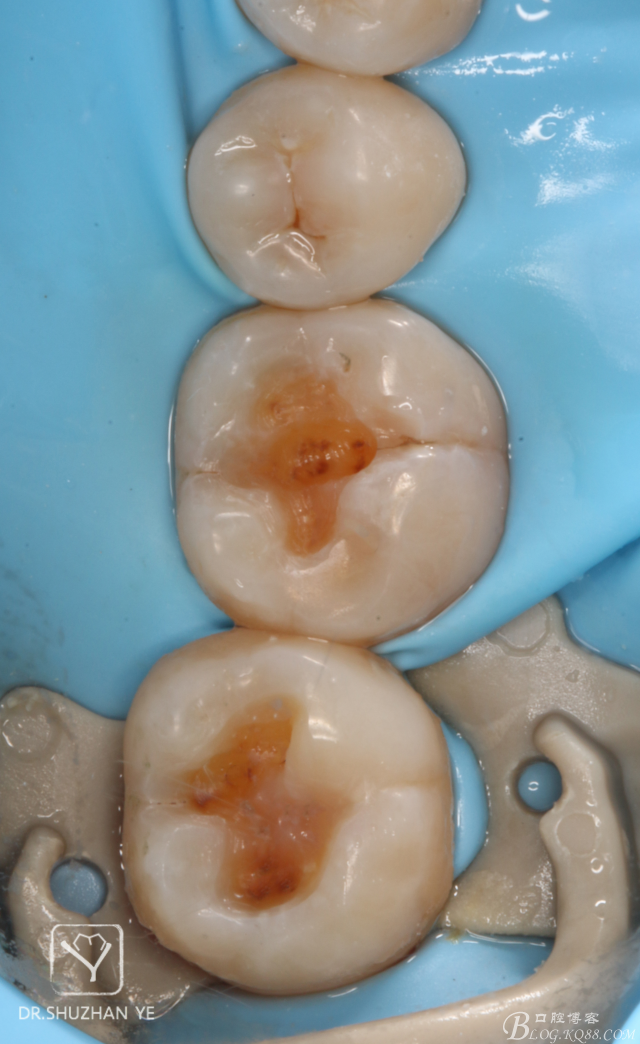

1、術(shù)前照片,46,47頜面齲壞,且頜面完整,無缺損

4、去齲后涂布齲顯示劑,保證去齲充分

20151205082558_85905.jpg

5、去齲完成

20151205082611_38012.jpg